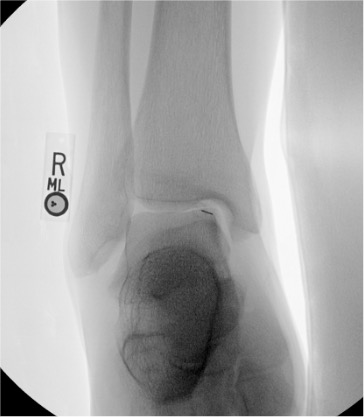

Elbow

Posterior (olecranon fossa)

Olecranon fossa with elbow flexed 90°; needle directed anteriorly into trochlear notch

8–10 mL